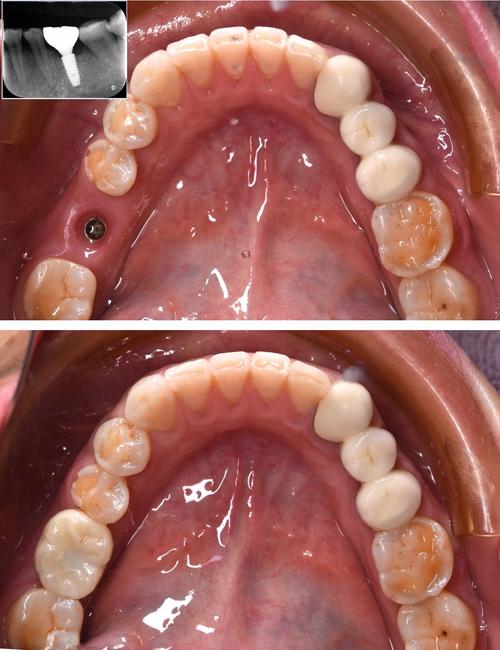

- 即刻手术:局部麻醉下拔除患牙,同期将种植体(如钛合金材质)植入牙槽骨,通过基台连接临时牙冠,即刻恢复牙齿形态;

- 术后维护:术后1周、1个月、3个月复查,观察骨结合情况,3-6个月后待种植体与骨组织融合,更换永久牙冠(如全瓷冠)。